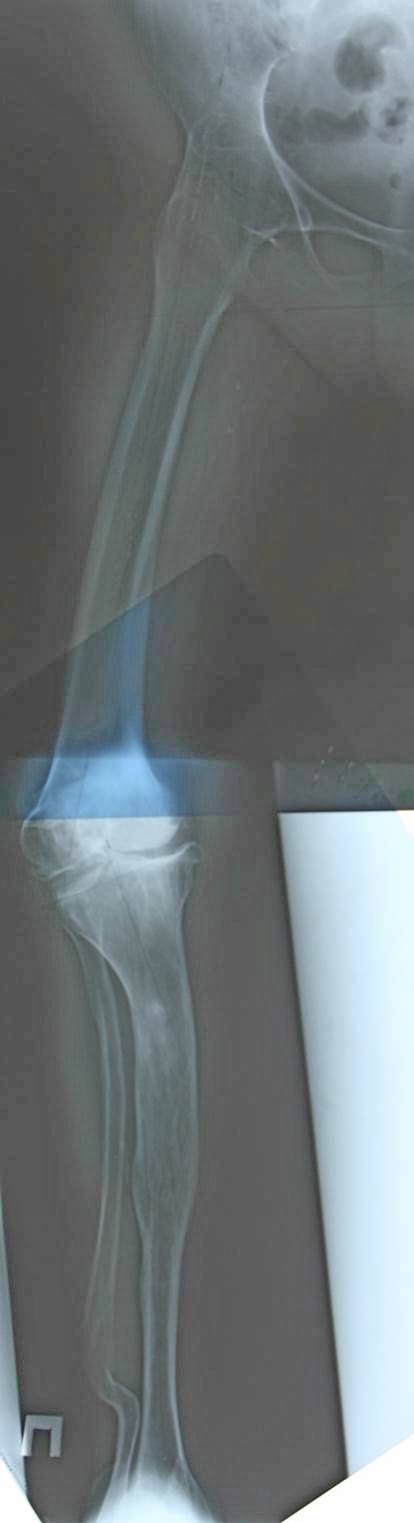

Артродез тазобедренного сустава неизвестной давности и сложная компенсаторная деформация конечности. Для принятия решения одной проекции не хватает. Дополнительно: общий таз и на всю длину конечности рентгенорамма с включением голеностопного. Отдельные снимки тазобедренного и коленного суставов.

На основании сравнительных данных механической оси конечности принимается решение. После длительно замкнутых суставов механика конечности адаптирована к этим условиям, и, нарушая, получаем совсем другие показатели.

Джолдас, спасибо за совет. Боковые проекции, конечно же, есть, но на них, скажем так, ничего примечательного. Равно как и таз с эндопротезом левого тазобедренного, который стоит весьма анатомично. В целом я тоже склоняюсь к тому, что никакие корригирующие остеотомии не нужны - они только помешают. Центр ротации правого тазобедренного сустава у нее где-то в позвоночнике и? как один из вариантов, планируется поставить обычные бедро и тибию ориентируя как раз на позвоночник.